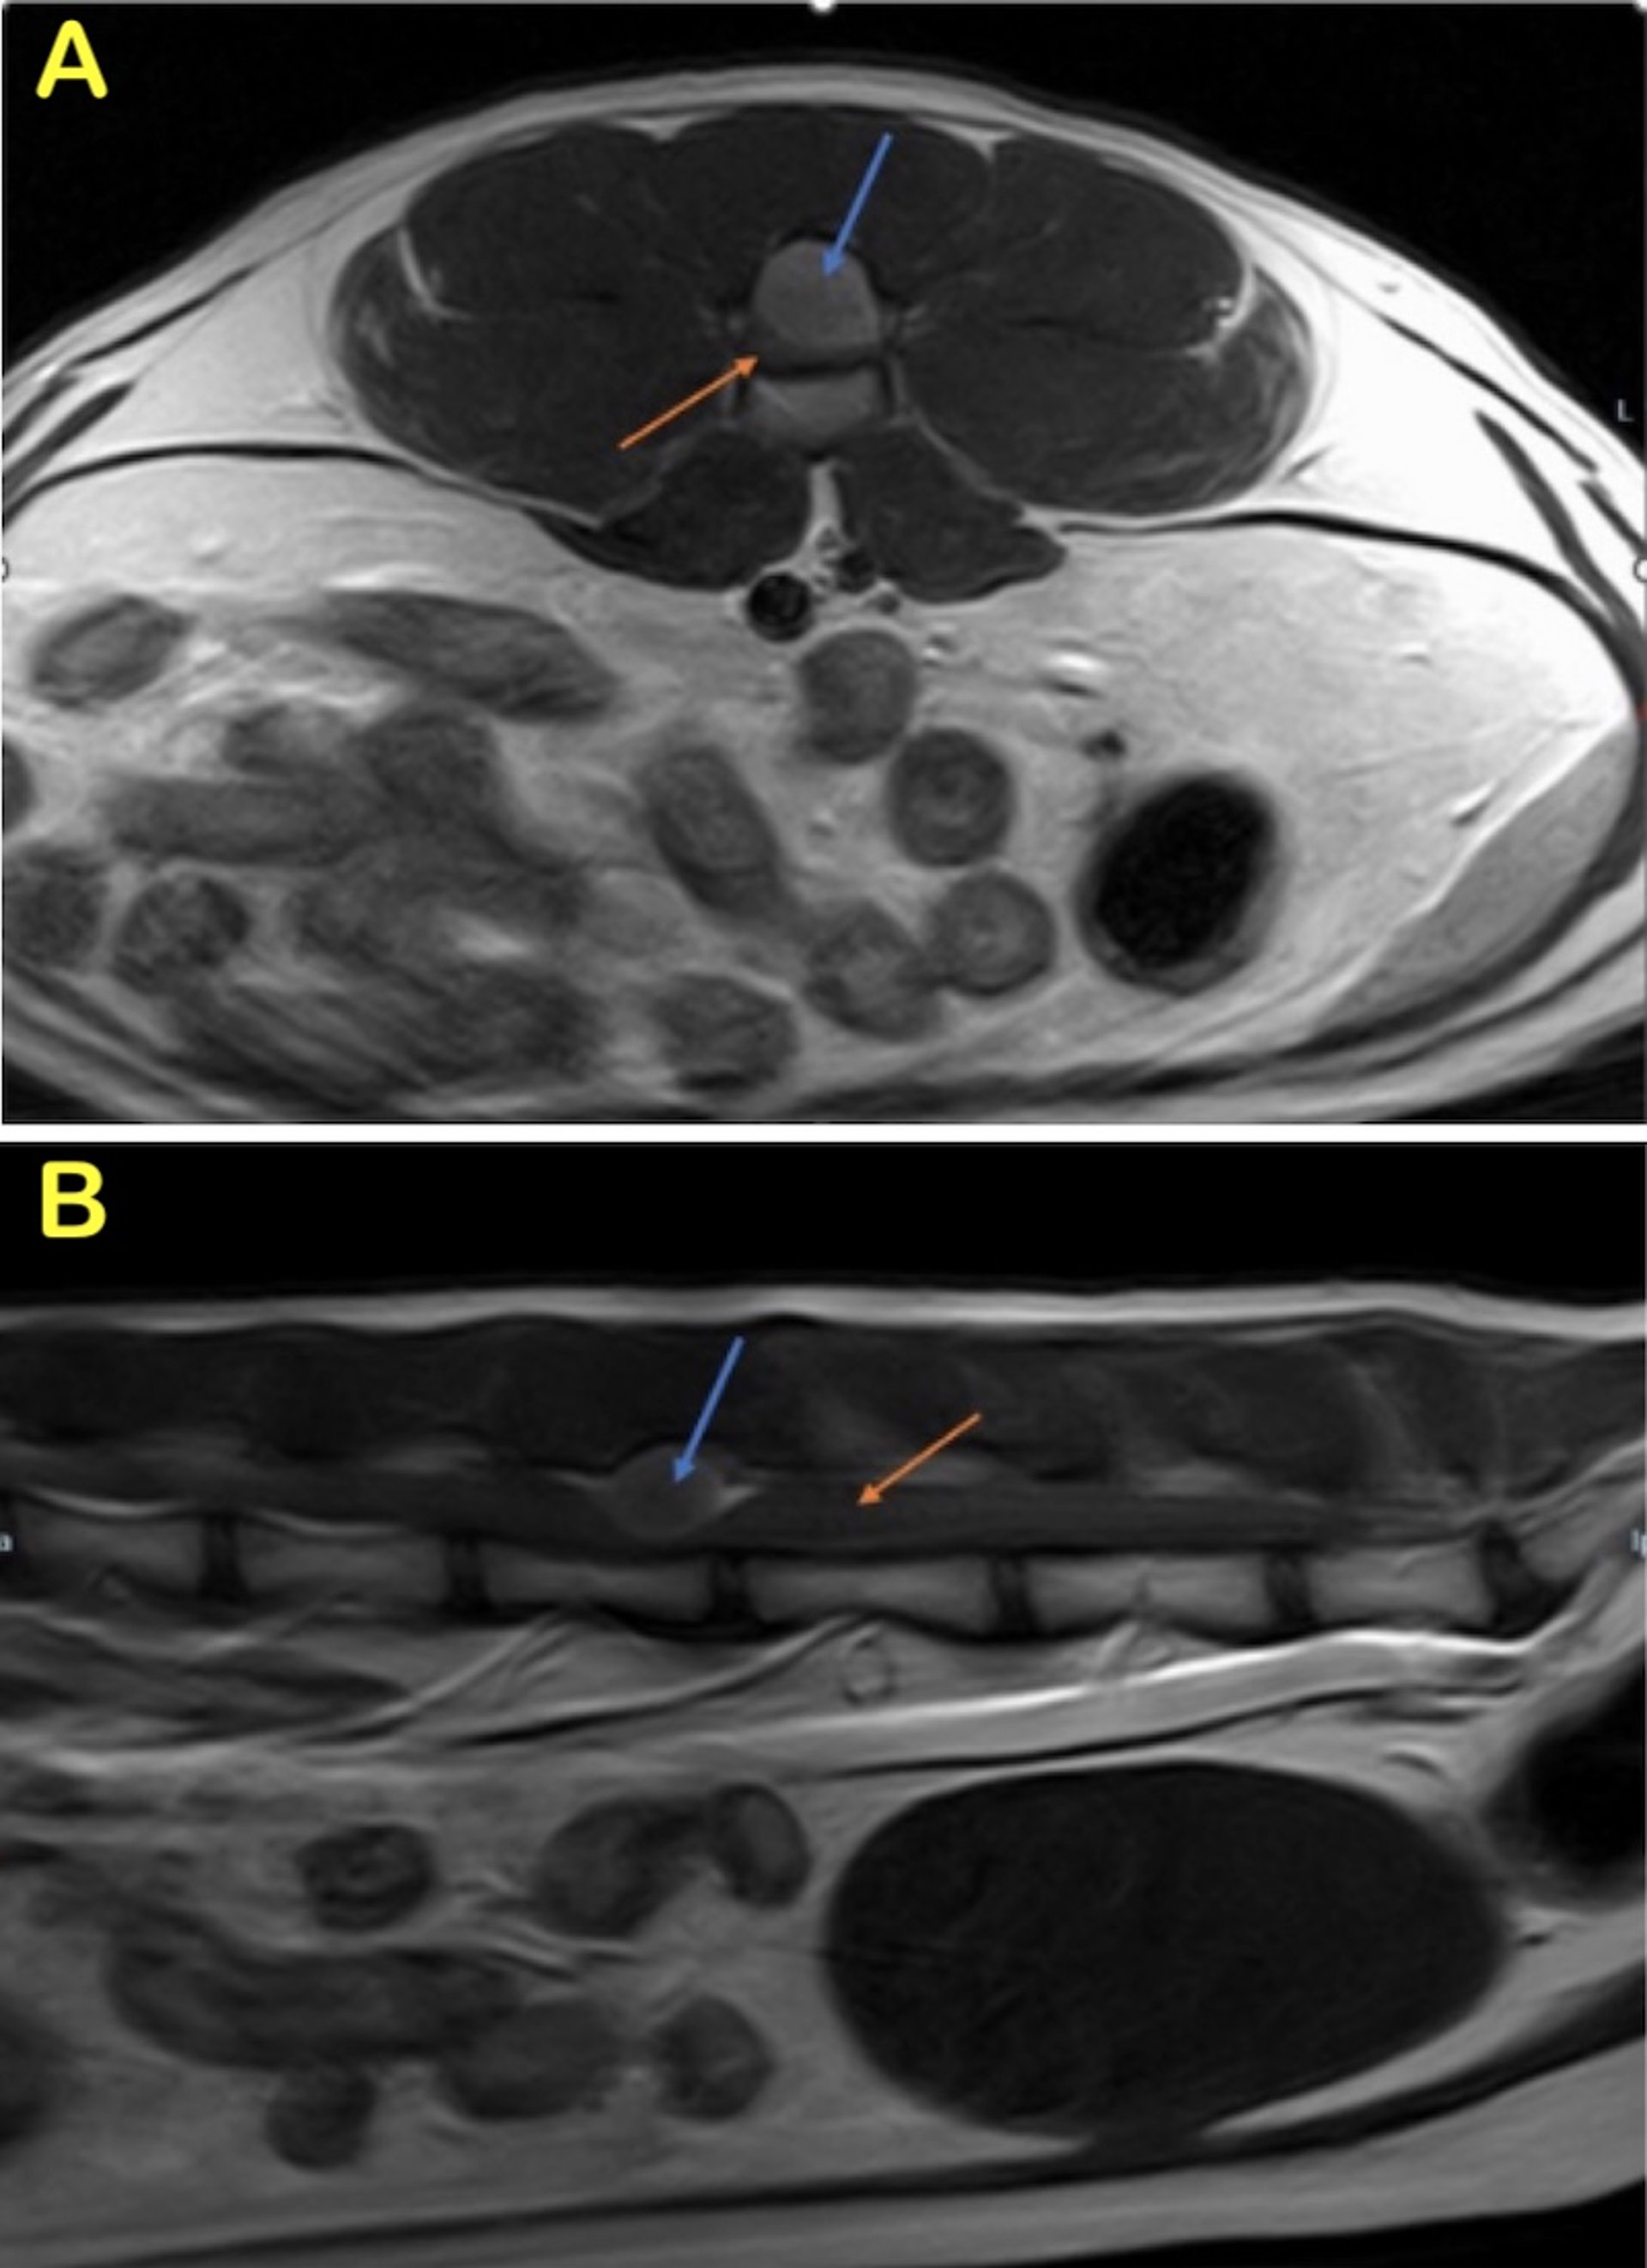

MRI features of astrocytomas and oligodendrogliomas show common findings that include ringlike contrast enhancement, cystic regions within the mass, and contact with the lateral ventricle. No magnetic resonance features have been able to reliably distinguish between these two tumor types. Contrast enhancement is reportedly more common in high-grade tumors (14). (See MRI of astrocytoma, dog)

Spinal cord tumors are relatively common in cats and dogs. They are generally classified according to their relationship with the spinal cord and meninges as extradural, intradural-extramedullary, or intramedullary. Depending on tumor location, any of the four spinal cord syndromes (ie, cervical, cervicothoracic, thoracolumbar, or lumbosacral) may be anticipated.

A primary intradural-extramedullary tumor with a predilection for T10 through L2 spinal cord segments in young dogs, particularly retrievers and German Shepherd Dogs, has been variously diagnosed as ependymoma, medulloepithelioma, nephroblastoma, or neuroepithelioma. The origin of this tumor is uncertain, and immunocytochemical studies have not supported a neuroectodermal origin. Monoclonal antibody studies suggest it may be a nephroblastoma.

The extramedullary masses are tan to grayish-white and 1–3 cm long. They are generally found dorsal and lateral to the spinal cord, may entrap the spinal roots, and may be accompanied by areas of hemorrhage and severe spinal cord compression.